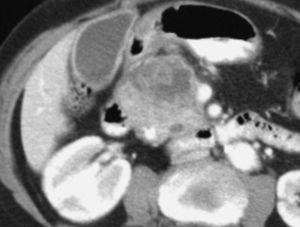

Aunque algunos autores no han observado diferencias significativas en cuanto al rendimiento de la TC helicoidal monofásica y bifásica en la detección y estadificación del cáncer de páncreas13, otros autores19,32, en series más largas incluyendo un mayor número de pacientes con tumores resecables, han aseverado el rendimiento de la TC helicoidal bifásica en la predicción de la resecabilidad del cáncer de páncreas, presentando valores predictivos para la resecabilidad tumoral entre 73,5% y 77% y valores de precisión diagnóstica entre 77% y 83%. Revisando específicamente los signos TC de infiltración vascular mediante TC helicoidal bifásica, Lu et al33, utilizando un sistema de gradación basado en la contigüidad del tumor con cada una de las estructuras vasculares (venas porta y mesentérica superior, o arterias hepática, mesentérica superior y tronco celíaco), presentaron un valor predictivo positivo del 95% y un valor predictivo negativo para la irresecabilidad neoplásica del 93% cuando consideraban infiltración vascular una contigüidad del tumor que excedía el 50% de la circunferencia del vaso en cuestión (fig. 4). A este mismo respecto Phoa et al34 describen como criterios de TC más fiables de invasión venosa la estenosis e irregularidad de la vena porta o la vena mesentérica superior, así como una contigüidad circunferencial del tumor con la vena porta superior a 90º (fig. 5). Los autores concluyen que la mejor combinación de criterios de TC fue la concavidad tumoral con afectación circunferencial vascular, con lo que presentan una sensibilidad del 61% y especificidad del 90%. Hough et al35 describieron el signo de la lágrima de la vena mesentérica superior, que consiste en una deformidad de la morfología redondeada de la vena adyacente al tumor en las secciones axiales, como indicativo de invasión venosa (fig. 6). Añadiendo este signo a los ya descritos de invasión venosa, consiguen aumentar la sensibilidad (60-91%) y el rendimiento diagnóstico de la TC (79-95%) sin modificar significativamente la especificidad (100-98%). No obstante, estos sistemas de gradación para el diagnóstico de la invasión vascular peripancreática tienen el inconveniente de la subjetividad a la que está sometida su lectura. Los casos extremos no presentan problemas de interpretación, pero la valoración del tumor rodeando al vaso alrededor de 90º de su circunferencia puede ser difícil, dado que además pueden existir bandas de infiltración de la grasa peripancreática que pueden rodear parcialmente un vaso o incluso continuarse sin plano graso de separación con el tejido tumoral. Estas bandas pueden representar cambios edematosos o inflamatorios locales (fig. 7). En este sentido, Valls et al19,36 presentan únicamente un 25% de valor predictivo positivo para la irresecabilidad tumoral para estas bandas perivasculares. Además se ha descrito la notoria variabilidad interobservador en función de su experiencia, que llega a alcanzar una diferencia de sensibilidad de hasta un 20% entre revisores experimentados y noveles14.

Fig. 6.--Estudio de tomografía computarizada con contraste endovenoso en fase venosa portal. Infiltración vascular de la vena mesentérica superior. Signo de la lágrima: deformidad focal de la morfología de la vena en contigüidad con el tumor.